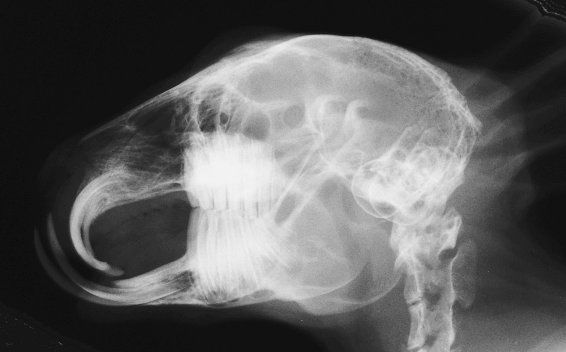

De boven- en onderkaak staan niet goed ten opzichte van elkaar, waardoor de natuurlijke slijtage van de tanden verkeerd loopt of geheel afwezig raakt. De snijtanden in de onderkaak groeien dan vóór de snijtanden van de bovenkaak en de snijtanden in de bovenkaak groeien in een krul naar binnen toe. Ook wanneer de tanden goed staan ten opzichte van elkaar, kan er malocclusie ontstaan ter hoogte van de kiezen, zgn trapvorming. Dit is zeer lastig te zien en wordt het best bekeken aan de hand van een röntgenfoto.

Normale occlusie:

Bij normale stand van de snijtanden rusten de tanden uit de onderkaak tegen de stifttanden bij gesloten mond. De kiezen hebben een mooi recht snijvlak, zonder hoogteverschilen (trapvorming).